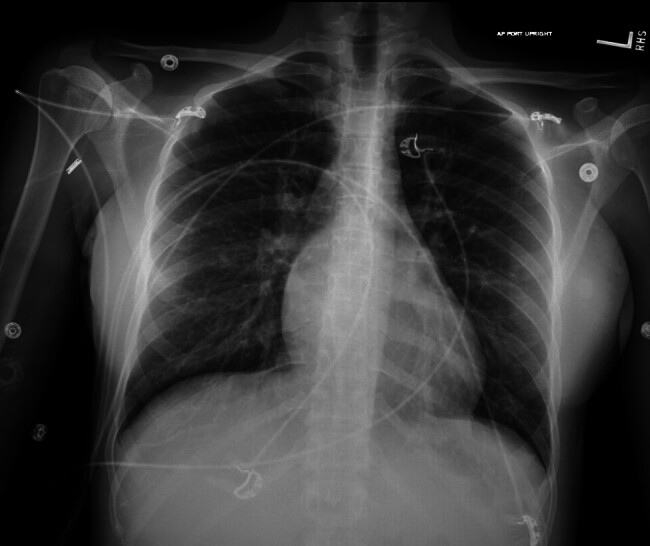

26岁女性,妊娠第1段,妊娠14周1天,出现阴道点滴和全身症状,包括心悸、呼吸短促、热不耐受、恶心和呕吐,持续2周。检查发现产妇心动过速,血压大范围升高,β人绒毛膜促性腺激素2,442,400 mIU/mL升高,促甲状腺激素抑制,T4升高,符合甲状腺风暴,可能伴有严重的先兆子痫。1经阴道超声提示部分臼齿妊娠;这后来被外科病理证实。本病例强调了葡萄胎罕见但严重的并发症,特别是部分臼齿妊娠,包括甲状腺风暴和叠加先兆子痫,强调了在三级保健中心与多学科团队管理的重要性,以优化产妇结局。2 3。

A 26-year-old woman, gravida 1 para 0 at 14 weeks' 1-day gestation, presented with vaginal spotting and systemic symptoms, including palpitations, shortness of breath, heat intolerance, nausea, and vomiting for 2 weeks. Workup revealed maternal tachycardia, severe-range blood pressure, elevated beta human chorionic gonadotropin of 2,442,400 mIU/mL, suppressed thyroid stimulating hormone, and elevated T4, consistent with thyroid storm with possible preeclampsia with severe features. 1 A transvaginal ultrasound suggested a partial molar pregnancy; this was later confirmed by surgical pathology. This case highlights the rare yet serious complications of hydatidiform mole, in particular, a partial molar pregnancy, including thyroid storm and superimposed preeclampsia, emphasizing the importance of management at a tertiary care center with a multidisciplinary team to optimize maternal outcomes. 2 3.